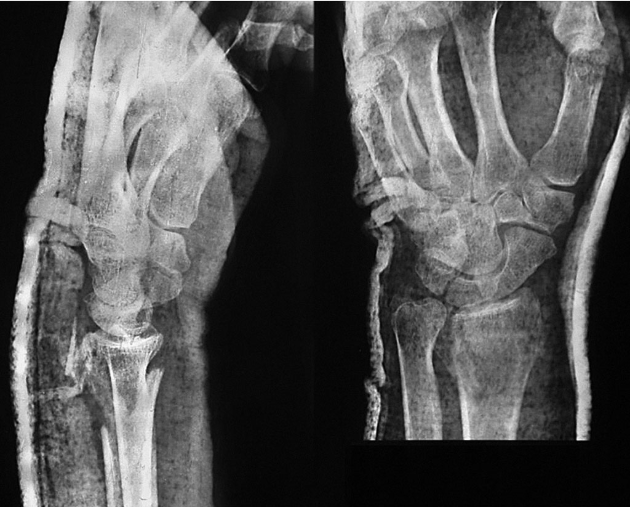

患者,女,51岁。因右腕摔伤后肿痛、畸形、活动受限,急诊就诊诊断为右桡骨远端骨折。行闭合牵引复位,石膏托外固定。拍片复查,桡骨远端背侧因骨折的粉碎性质而缺损巨大,背侧的皮质骨碎片向远端移位至桡腕关节间隙水平并嵌于腕背软组织中无法闭合复位(图2-1)桡骨远端背侧因缺乏可靠的皮质骨支撑而存在骨折继发移位、掌倾角向背侧倾斜且移位的皮质骨碎片潜在刺激背侧软组织、磨损伸肌腱的风险,增加发生关节疼痛和功能障碍的可能性,于是行桡骨远端骨折切开复位,人工骨植入,超关节外固定架固定术。

图2-1 桡骨远端背侧因骨折的粉碎性质而缺损巨大,背侧的皮质骨碎片向远端移位至桡腕关节间隙水平并嵌于腕背软组织中无法闭合复位